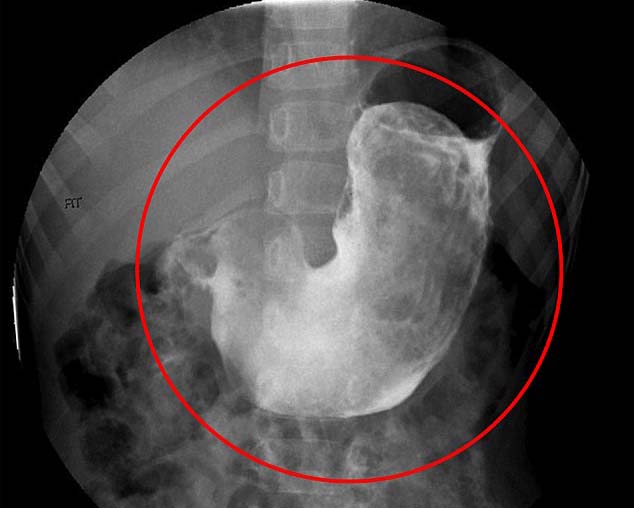

Egy Rapunzel-szindrómában szenvedő kislány röntgenképe, aki 2015-ben műtöttek meg

A nő gyomra feldagadt, mintha folyadékkal és gázzal telt volna fel. Egy éven át alig evett, nyolc kilogrammot fogyott és mire kórházba került, már egy falat ételt sem tudott lenyelni – olvasható a BBC hírportálján. Az orvosok, akik az esetről a British Medical Journal (BMJ) című brit orvosi folyóiratban számoltak be, azonnal vért adtak a nőnek, hogy kezeljék kóros vérszegénységét. Ezt követően hasüregi műtétet hajtottak végre rajta, akkor került elő gyomrából a 15-ször 10 centiméteres, sűrű hajgombóc és egy kisebb, 4-szer 3 centiméteres a vékonybélből. Az elzáródást sikerült megszüntetni, a nőnek proteinben gazdag diétát írtak elő, ami felépülését segíti.